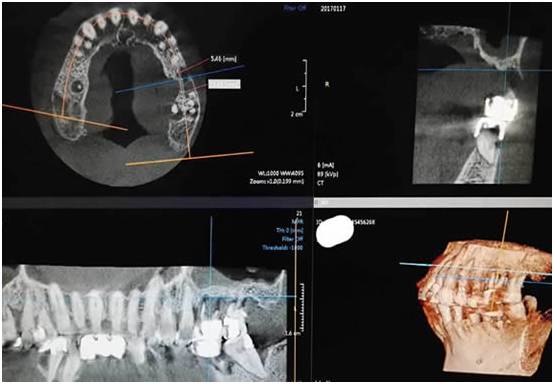

图一:术前ct检查(上颌窦底只有不到2毫米厚度、上颌窦黏膜有炎症性水肿)

1、上颌窦只有不到两个毫米厚度的骨头了

2、上颌窦黏膜有炎症性水肿